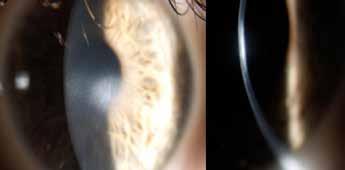

Ongoing research and technological advances in biomarking and genetic therapies are paving the way for innovative treatments that could transform keratoconus in the near future, according to Koji Kitazawa MD, PhD.

“Significant challenges remain, but we are making steady progress. Biomarkers play a pivotal role in the diagnosis, monitoring, and potential treatment of keratoconus— while gene therapy holds promise as a potential cure for keratoconus by addressing the genetic causes of the disease,” Dr Kitazawa said.

Dr Kitazawa defined biomarkers as measurable indicators of a biological condition or state.

“In the context of disease, they can be substances or processes indicating the presence, stage, or progression of a disease,” he explained. “Biomarkers can identify keratoconus early, even before significant symptoms appear. They can help with monitoring disease progression and the effectiveness of the treatment. Biomarkers also allow for a more personalised medical approach, leading to better clinical outcomes and reduced side effects.”

These biomarkers can be broken down into three broad subcategories: structural, proteomic, and genetic.

“Structural biomarkers identify changes detected through imaging techniques such as corneal topography or tomography that show characteristic thinning or bulging of the cornea,” he said. “Proteomic biomarkers show protein expression levels that differ between healthy and keratoconus-affected corneas, and genetic biomarkers show variations or mutations in specific genes associated with keratoconus.”

To highlight the potential utility of structural biomarkers in keratoconus, Dr Kitazawa and team evaluated the diagnostic performance of the different indices obtained between normal eyes and keratoconic eyes using anterior segment optical coherence tomography.

“Our findings revealed the anterior surface and posterior surface ratio was smaller in forme fruste keratoconus and keratoconic eyes, suggesting—theoretically—that the posterior surface area became enlarged compared to the anterior surface at the initial stage of the disease,” he said.